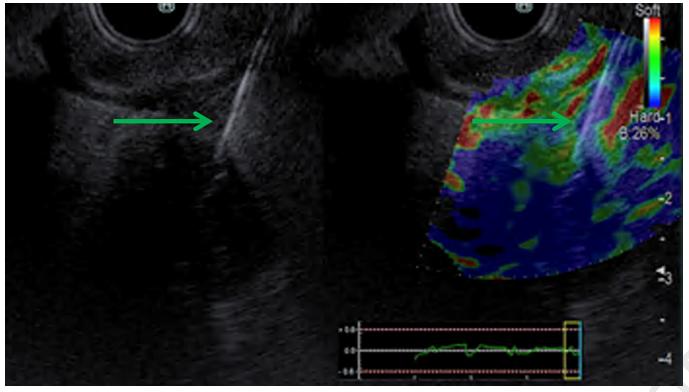

同时可使用弹性成像技术,以确保细针在肿瘤内的放置(如图2所示)。一旦消融光纤在肿瘤内所需位置就位,激光就被激活,以50 J/cm的速度照射333 s。术后第2天进行CT检查,在第1、2和14天监测不良事件发生情况。

图2. 弹性成像证实超声内镜引导下细针穿刺进入肿瘤以进行光动力治疗。A,在内镜超声下,胰头肿块内可见19号穿刺针(绿色箭头)。B,弹性成像显示胰头肿块与周围组织相比硬度增加(蓝色)。